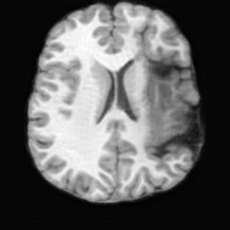

Healthy w/Lesion MaskPathologicalDifferencew/o LCGw/ LCG(a)Refer to captionRefer to captionRefer to captionRefer to captionRefer to captionRefer to captionHealthy w/Lesion MaskPathologicalDifferencew/o LCGw/ LCG(b)Refer to captionRefer to captionRefer to captionRefer to captionRefer to captionRefer to caption

Figure 7: Ablation study of Lesion Consistency Guidance (LCG). Without LCG, the generated pathological regions are indistinct and show weak pathological expression in both examples.

Lesion Consistency Guidance. Fig. 7 illustrates the impact of Lesion Consistency Guidance (LCG) for healthy-to-pathology editing. Without LCG, the generated lesion regions appear blurry around lesion boundaries, and the pathological patterns are less distinct, resulting in ambiguous lesion localization and weak pathological expression. Incorporating LCG produces lesions with more precise localization and well-defined shapes that better align with the given lesion masks, as well as textures and contrasts that exhibit stronger pathological characteristics. These results demonstrate that LCG effectively enforces lesion-aware conditioning, enhancing both spatial and semantic consistency of the generated pathological regions.